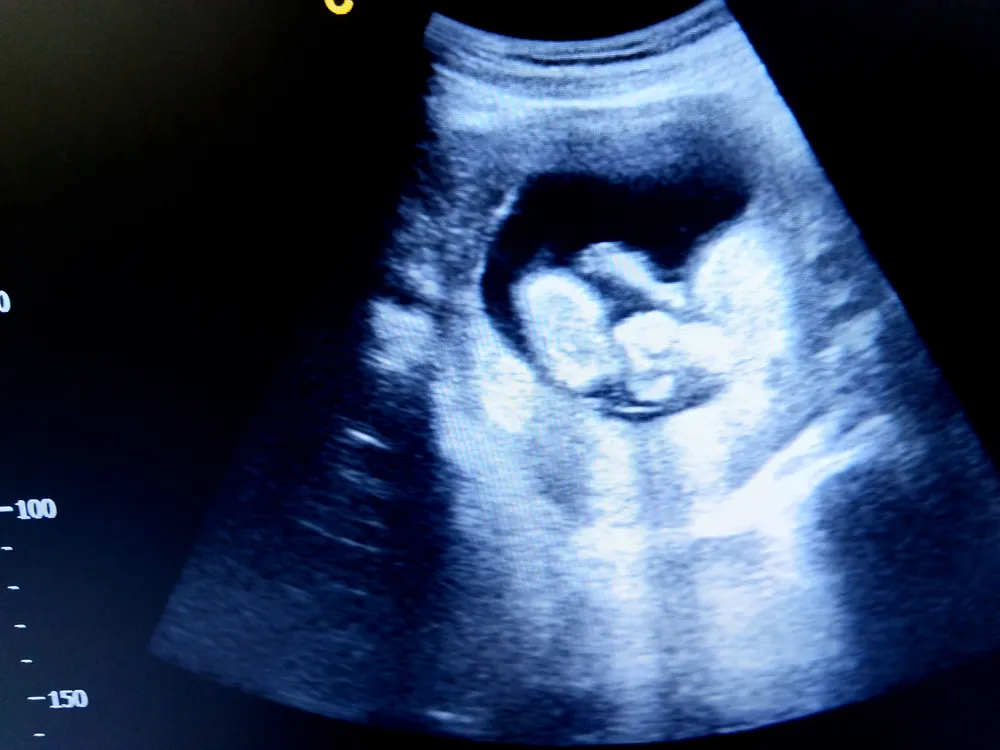

Thai nhi 13 tuần tuổi phát triển như thế nào?

1. Chiều dài, cân nặng của thai nhi 13 tuần tuổi

Nếu bạn đang thắc mắc thai nhi 13 tuần nặng bao nhiêu hay thai 13 tuần to bằng quả gì? Theo các chuyên gia sản khoa, thai nhi trong bụng mẹ có kích thước tương ứng với một quả mận. Con sẽ có kích thước như sau:

- Cân nặng khoảng 25g

- Chiều dài từ đầu đến mông khoảng 7,4cm.

- Khi thai nhi nằm trong bụng mẹ, tay chân của em bé hơi co vào thân mình, lưng có thể cong hoặc thẳng, đầu khi cúi khi ngửa. Do đó, việc hình dung thai nhi 13 tuần như quả mận là đang hình dung em bé theo 1 khối co lại và ngắn lại.

- Việc tính chiều dài thai nhi chỉ mang tính chất tương đối và áp dụng cho thai trong quý 1, từ 14 tuần trở đi, các cử động của thai nhi tương đối nhiều, chân tay cũng phát triển rõ hơn và có cử động gập duỗi, lúc này việc tính các thông số sinh trắc thường ít sử dụng chiều dài đầu mông hay chiều cao (từ đầu đến gót chân).

9. Chuyển động của thai nhi 13 tuần

- Em bé đang di chuyển xung quanh trong buồng ối. Lúc đầu, các chuyển động rất giật cục và ngẫu nhiên nhưng sau đó các cử động bắt đầu có vẻ nhịp nhàng hơn.

- Bạn có thể không cảm thấy bất kỳ chuyển động nào cho đến khoảng tuần thứ 17 của thai kỳ.